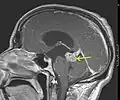

1. Astrocitoma de bajo grado del mesencéfalo (lámina tecti), resonancia magnética sagital ponderada en T1 después de la administración de medio de contraste: el tumor está marcado con una flecha. Los espacios del LCR frente al tumor se expanden debido a la hidrocefalia interna inducida por compresión.. -